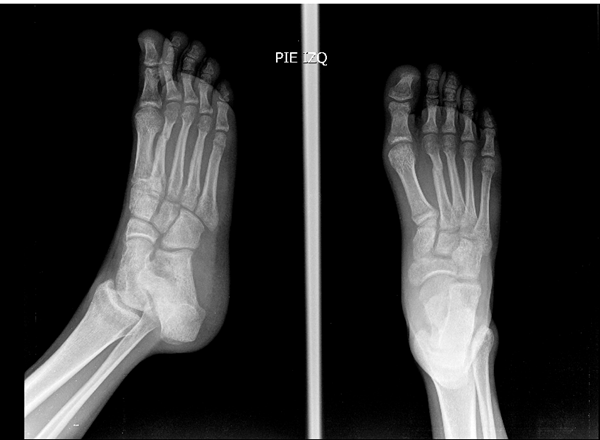

El pasado 2 de octubre tuve una fractura transversa en el tercio medio distal del 2 metatarsiano, el 11 de noviembre me quitaron la inmovilización pero siento que eso tiene crepitación, la fractura se desplazó un poco hacia abajo, ¿es normal que sienta que traquea?HAROLD IVANOVICH